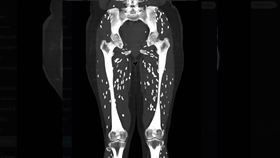

泰籍移工吃生豬肉 一照…腿內竟長蟲

一名42歲的泰籍移工來台工作多年,偶爾會與同鄉生食豬...